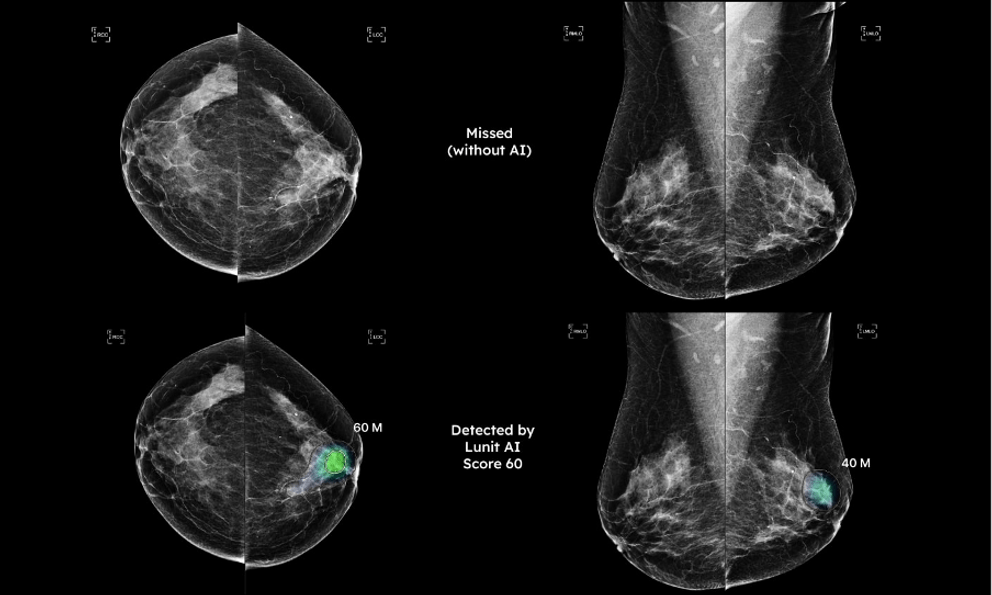

AI tầm soát ung thư vú ứng dụng trong quy trình chụp X-Quang tuyến vú, đã được FDA cấp phép lưu hành theo mã K211678 và đạt chứng nhận tiêu chuẩn châu Âu CE, có khả năng nhận diện chính xác lên đến 97% đối với các tổn thương có kích thước rất nhỏ (từ 2mm) mà mắt thường dễ bỏ sót trong môi trường đọc phim tiêu chuẩn, có khả năng phát hiện các tổn thương ung thư ở thể không tạo khối - dạng tổn thương cực kỳ khó nhận biết trên phim X-quang thông thường, thường là nguyên nhân dẫn đến các trường hợp âm tính giả (bỏ sót bệnh).